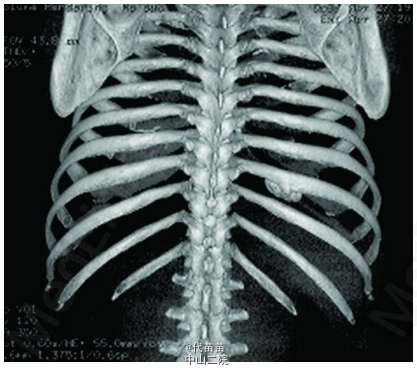

患者男性,40 岁。因体检发现肋骨肿块入院。患者无其它特殊症状,血生化检查基本正常,无放、 化疗史及Paget病史。CT检查示右侧第九后肋骨旁一团块状混杂高密度影,肿块边界尚清,位于肋骨表面,非髓内生长,向胸腔隆起,位于壁层胸膜与肋骨之间,与骨皮质有蒂相连(图 1、2)。临床考虑良性病变骨软骨瘤可能,遂行手术切除一段肋骨及表面肿块,送病理检查。 病理检查:眼观:送检肋骨1段,长9cm,宽2cm,骨表面隆起卵圆形肿块,4 cmX2 cmX2 cm 大小,质硬,切面灰白色,实性,与骨皮质有蒂相连,蒂部骨皮质浸润(图 3)。镜检:肿瘤由大量狭长且具平行排列倾向的高分化骨小梁构成,以编织骨为主,部分骨小梁已成熟为板层骨,大部分骨小梁周围缺乏成骨细胞被覆,部分区域已逐渐移行为有成骨细胞被覆的板层骨,瘤骨内可见骨重建过程中形成的粘合线,即所谓“Paget” 现象(图 4)。骨小梁间充满低细胞性纤维组织间质,梭形成纤维细胞形态温和,细胞核卵圆形,缺乏不典型性,部分肿瘤性骨小梁之间有脂肪髓形成,但无造血组织。肿瘤表面的骨样组织较幼稚,深部为相对成熟的粗大编织骨和板层骨(图 5),蒂部皮质和近皮质的髓腔内有局灶性肿瘤浸润(图 6)。肿瘤内含多灶性高分化软骨,软骨细胞排列紊 乱无极性,由于部分软骨位于肿瘤表面,故影像学和病理学类似骨软骨瘤改变。病理诊断:右侧第九后肋骨旁骨肉瘤。 骨旁骨肉瘤临床表现为骨表面缓慢生长的无痛性肿块,质硬,病程较长,可达数年。骨旁骨肉瘤预后较好,其5 年生存率达91% ,最佳治疗方案是大块肿瘤完整切除,切除范围应包括肿瘤周围的正常组织和软组织内的卫星病灶。若不完整切除则很容易复发。复发性肿瘤易发生去分化改变,称去分化骨旁骨肉瘤,其预后类普通型骨肉瘤,治疗原则和普通高级别骨肉瘤一致。 骨旁骨肉瘤可以说是骨肉瘤中的“异类” ,因为其不仅分化好,类似良性骨病,而且在骨表面生长,在病理诊断时须注意与以下三种良性骨病鉴别:(1)纤维结构不良。本例虽然部分肿瘤性编织骨呈不连续的字母状结构,在编织骨之间为高分化纤维,类似于纤维结构不良,但纤维结构不良是一 种纤维化生骨,伴有骨的成熟障碍,不会成熟为板层骨,也不会出现板层结构瘤骨在改建塑型过程中形成“Paget”现象。本例镜下见瘤骨比较成熟、 粗大,大部分相互连接成网,并有平行排列倾向,肿瘤表面骨样组织幼稚,深部较为成熟,并形成板层骨,成熟瘤骨内能见到“ 孕葬早藻贼” 现象。此外纤维结构不良均在髓内生长,不会在骨表面外生性生长,故影像学改变即可排除纤维结构不良。(2)骨软骨瘤。本例肿瘤内含有少量高分化软骨组织,由于部分软骨位于肿瘤表面,需与骨软骨瘤鉴别。骨软骨瘤蒂部的骨皮质常有缺损,肿瘤内的松质骨与宿主骨的正常松质骨相连续,二者相互融合。而骨旁骨肉瘤常环绕宿主骨在骨膜外生长,与髓腔不相通,肿瘤与骨密质之间有狭长的透亮带,即残存的骨膜;骨软骨瘤软骨帽下是由软骨化骨形成的松质骨小梁,骨小梁间隙内充满正常的造血性红髓或脂肪性黄髓,而缺乏骨旁骨肉瘤的成纤维细胞成分。同时骨旁骨肉瘤内的软骨组织、 结构和分布随意紊乱,缺乏骨软骨瘤明显的分层结构。(3)骨旁骨瘤。大多位于颅骨表面或副鼻窦内,分化成熟的骨小梁之间为脂肪细胞和小血管,缺乏纤维母细胞性间质。